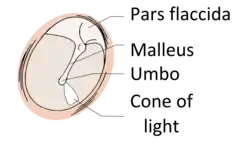

Regions

The eardrum is divided into two general regions: the pars flaccida and the pars tensa.[3] The relatively fragile pars flaccida lies above the lateral process of the malleus between the Notch of Rivinus and the anterior and posterior malleal folds. Consisting of two layers and appearing slightly pinkish in hue, it is associated with Eustachian tube dysfunction and cholesteatomas.[4]

The larger pars tensa consists of three layers: skin, fibrous tissue, and mucosa. Its thick periphery forms a fibrocartilaginous ring called the annulus tympanicus or Gerlach's ligament.[5] while the central umbo tents inward at the level of the tip of malleus. The middle fibrous layer, containing radial, circular, and parabolic fibers, encloses the handle of malleus. Though comparatively robust, the pars tensa is the region more commonly associated with perforations.[6]

Umbo

The manubrium (Latin: handle) of the malleus is firmly attached to the medial surface of the membrane as far as its center, drawing it toward the tympanic cavity. The lateral surface of the membrane is thus concave. The most depressed aspect of this concavity is termed the umbo (Latin: shield boss).[7]

When the eardrum is illuminated during a medical examination, a cone of light radiates from the tip of the malleus to the periphery in the anteroinferior quadrant, this is what is known clinically as 5 o'clock.